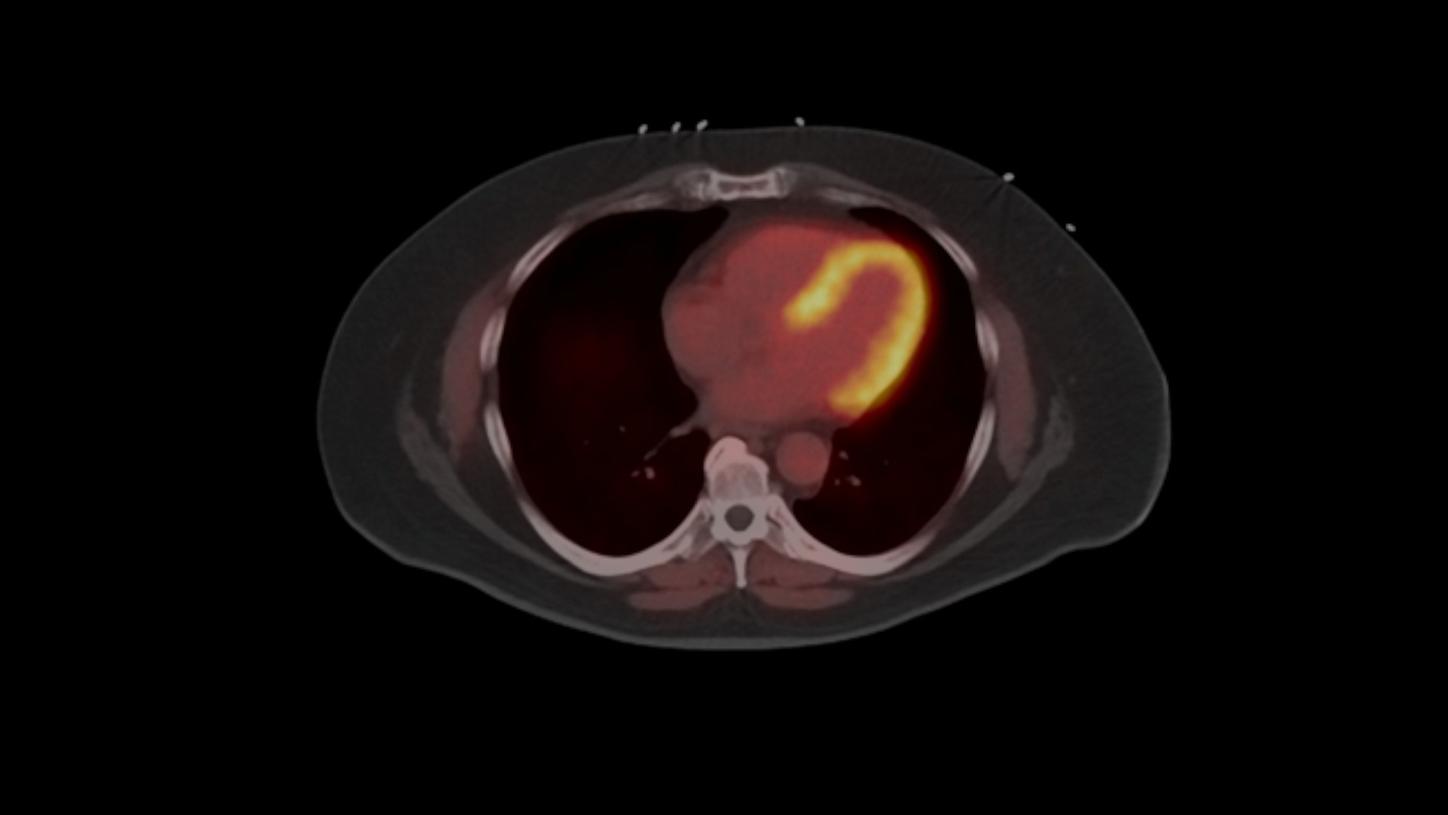

Biograph Vision and Biograph Vision Quadra are not commercially available in all countries. Future availability cannot be guaranteed. Please contact your local Siemens Healthineers organization for further details.

[a] The tracer used in this case is a research pharmaceutical. It is neither recognized to be safe and effective by the FDA nor commercially available in the United States or in other countries worldwide. Its future availability cannot be guaranteed. Please contact your local Siemens Healthineers organization for further details.